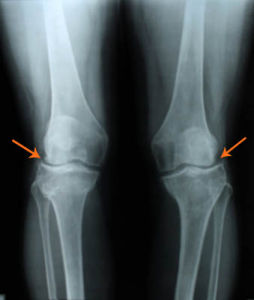

典型查體所見為髕骨碾磨試驗(+);有磨檫音,但大關節間隙無壓痛。繼發滑膜炎可出現關節積液,此時浮髕試驗陽性。病程長者,有股四頭肌萎縮。臨床X線檢查常有不同程度的骨質增生,X線軸位檢查可見髕骨側傾或半脫位(箭頭所示),外側間隙變窄,髕股關節外側過量長期的磨損,會造成相應關節軟骨下骨硬化,髕骨側位X線片可見“月芽樣”骨硬化影(圖3箭頭所示)。CT或磁共振(MRI),也可看到髕骨軟骨破壞現象(圖3箭頭所示)。

上述臨床症狀加上典型的膝關節軸位檢查可見髕骨側傾或半脫位,髕股關節外側間隙變窄,即可診斷。鑑別診斷